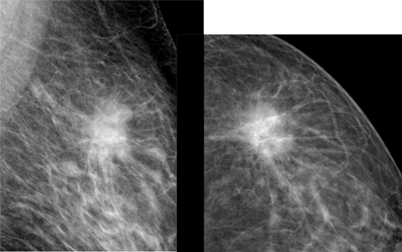

The aim of this research is to describe the intrinsic subtypes of breast cancer which has an appearance of spiculated mass on mammography. There were 59 patients that met the inclusion criterions at DR. Soetomo General Hospital, Surabaya between January 2017 and December 2018 (Figure 1−4). The youngest subject is 34 years old and the oldest being 73 years old with the average age of 52.1 years old. We divided the patients into three age groups, below 40 years old, 40-50 years old and above 50 years old. The average age of subtype Luminal A were the oldest with 53.6 years old, 52.9 years old in Luminal B, 47.4 years old in the basal-like and the youngest of which 46.8 years old in the HER2+subtype (Table 1) (Figure 5).

Figure 2 The mammographic appearance of spiculated mass in subject with pathological subtype Luminal B.